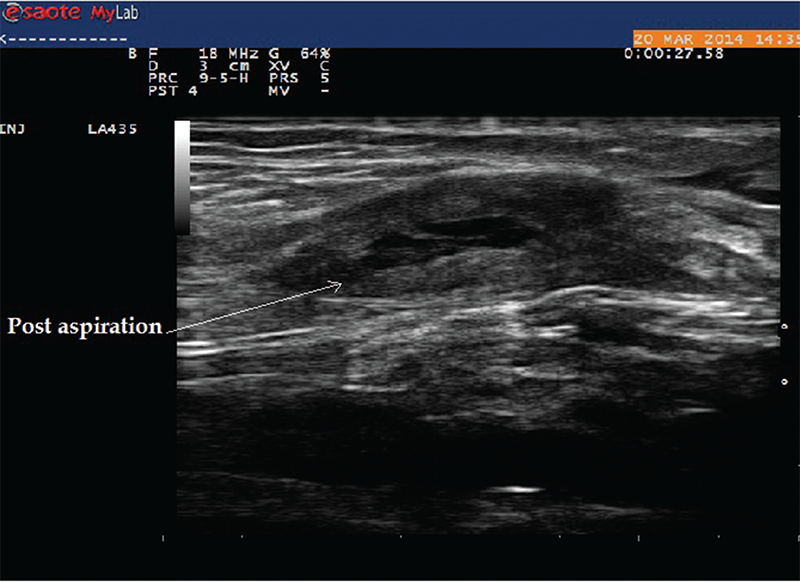

Case 4

A 75-year-old female with a history of seronegative RA on low-dose prednisone, hydroxychloroquine and leflunomide presented to the rheumatology office with complaints of posterior knee pain and swelling, which had gradually worsened in the past month. She was compliant with her medications, and there was no recent change in her medications. Ultrasound of her knee demonstrated a large Baker’s cyst, and ultrasound-guided aspiration of the fluid demonstrated class I fluid. Typically, on a transverse view, boundaries of Baker’s cyst are formed by semimembranosus and semitendinosus of the medial aspect and medial gastrocnemius on the lateral aspect. Ultrasound allowed for diagnosis and therapeutic intervention during the same visit without the need to refer to radiology (see Images 9 and 10).

Image 10: This image was taken after aspiration of the fluid from the cyst.